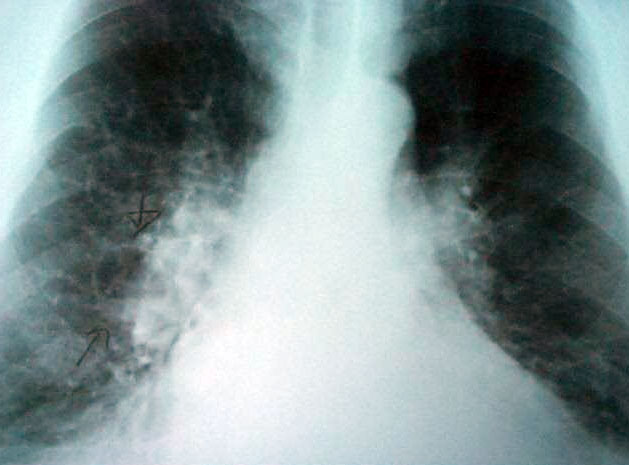

El 27 de marzo se celebra el Día de la Enfermedad Pulmonar Obstructiva Crónica (EPOC), patología que en España afecta a un millón y medio de personas y que actualmente representa la cuarta causa de mortalidad.